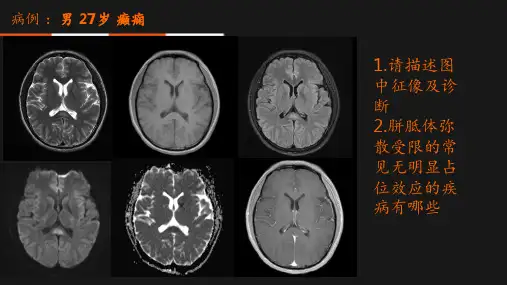

(1c)FLAIR 轴面 病变以高信号为主,仅少许部分信号强度衰减

(1d)T1WI矢状面 病变的“三明治”状特征

• MRI表现为:T1WI多为等信号或稍低信号, T2WI呈高信号, 增强后胼胝体可有不同程度强化。 FLAIR像呈现的周围高信 号环、中央低信号核。

MBD的急性期征象:胼胝体增大尤其是膝部膨胀性改变。

MBD特征性表现:胼胝体中层变性类似“三明治”状改变。